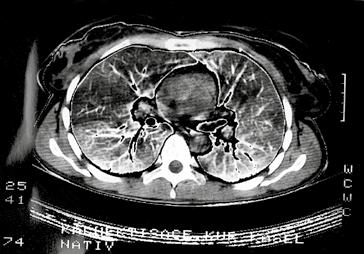

Kromě nakladatelství a výtvarníka se o definitivní podobu třetího dílu učebnice zasloužili mnozí odborníci. Za poskytnutí rtg snímků jsem již od vzniku 1. vydání 3. dílu učebnice vděčný Radiodiagnostické klinice 1. LF UK a paní doc. MUDr. Běle Drugové, DrSc., z radiodiagnostického oddělení Nemocnice Na Homolce. Za vynikající mikrofotografie z vývoje oka děkuji panu prof. MUDr. Františku Vrabcovi, DrSc., který mi je poskytl pro tuto knihu. Panu prof. MUDr. Oldřichu Eliškovi, DrSc., a paní doc. MUDr. Miloslavě Eliškové, CSc., děkuji za poskytnutí podkladů z jejich studií pro vytvoření obrazů mízního odtoku ze srdce. Panu doc. MUDr. Jaromíru Hradcovi, CSc., ze III. interní kliniky 1. LF UK děkuji za poskytnutí echokardiografických obrazů srdce. Upřímně děkuji též oběma spolupracovníkům, panu prof. MUDr. Rastislavu Drugovi, DrSc., a panu prof. MUDr. Miloši Grimovi, DrSc., za porozumění a sympatickou spolupráci na tomto vydání knihy. Studentům, učitelům anatomie i lékařům přeji, aby jim kniha sloužila jako užitečný průvodce a pomocník při studiu tohoto náročného oboru.